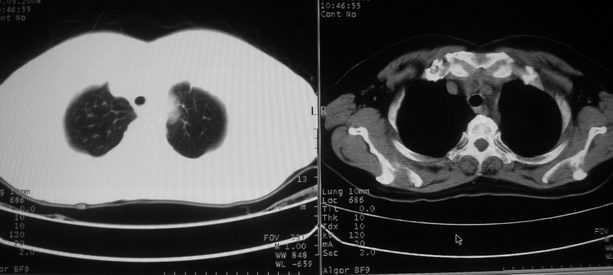

以下是引用zhangzhongshou在2008-5-22 12:51:00的发言:[br]左肺上叶肺癌并左侧胸腔积液可能性大。

以下是引用w_jianhua在2008-5-22 12:59:00的发言:[br]1.左肺上叶肺癌并左侧胸腔积液可能性大。2不除外支气管内膜结核并包裹性胸腔积液,建议支气管镜检3.左肺下叶肺大泡,肺气肿